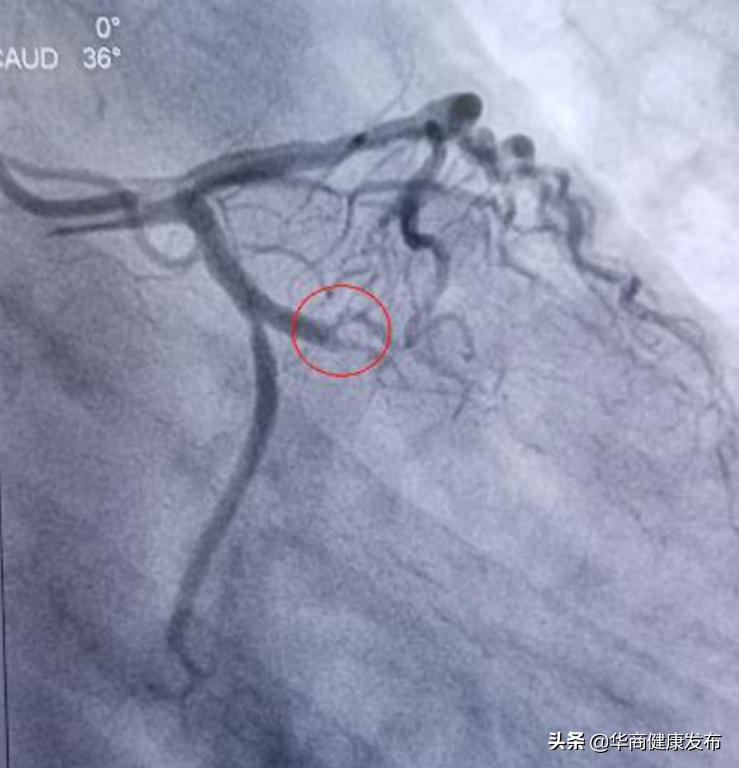

2021年12月27日晚、12月30日、12月31日西安交大二附院整建制医疗二队、三队和重症医学小组共计135名队员分批进驻市人民医院,以加强市人民医医疗救治力量。全体队员深入学习贯彻习近平总书记关于疫情防控工作的重要指示批示精神,认真落实孙春兰副总理要求,坚持人民至上、生命至上,在最短的时间内完成接管病区,在最短的时间让患者得到了有效的治疗。2022年1月13日从长安区医院急诊转入一位54岁男性新冠肺炎合并急性心梗患者,巩守平书记第一时间组织心脏介入团队,启动应急预案,由心内科高登峰教授带队,范博渊医生、李婧和徐一涛护师组成心脏介入应急团队,立即为患者实施CAG+PCI术,35分钟内打通闭塞血管,缓解了患者症状,彰显了交大二院人的高超医技和职业素养,获得了国家专家组及省市卫健委的高度认可。